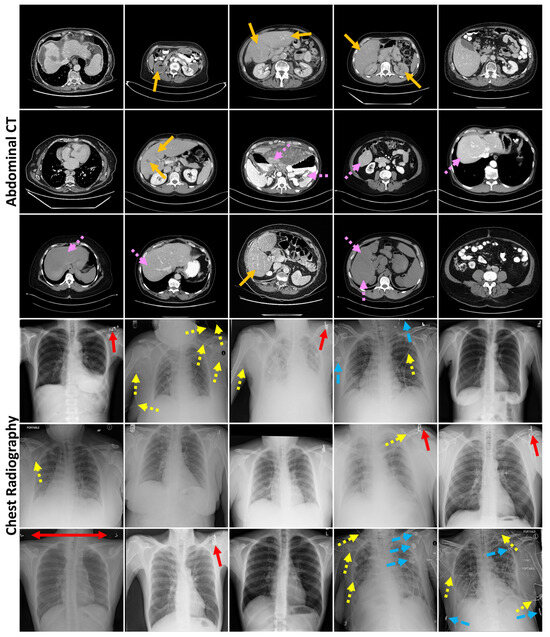

3.4. Localization of Anomalous Regions